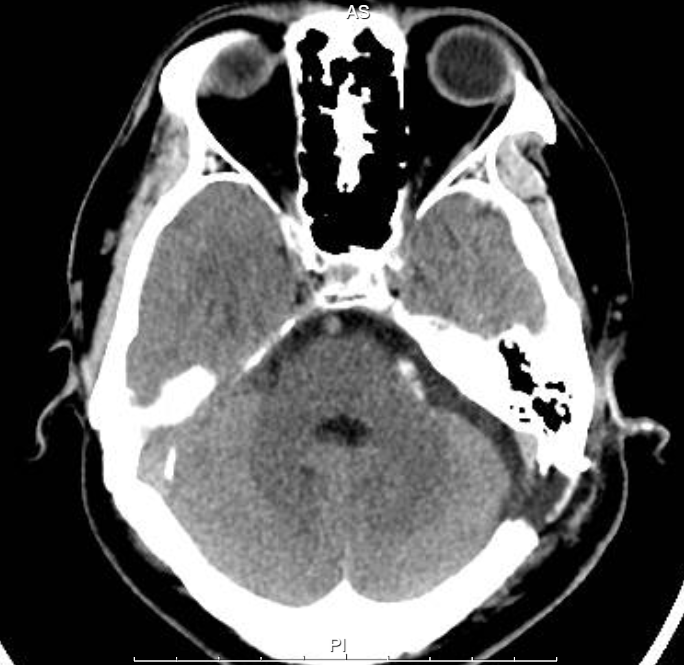

患者李某某,因“左眼睑不自主抽动9个月,加重2个月”入院。术前MRI检查明确血管神经压迫关系。经充分术前评估,神经外科团队为其施行“左侧面神经微血管减压术”。

图片 2.png

术后患者左眼睑抽搐立即消失,复查CT显示颅内情况良好。